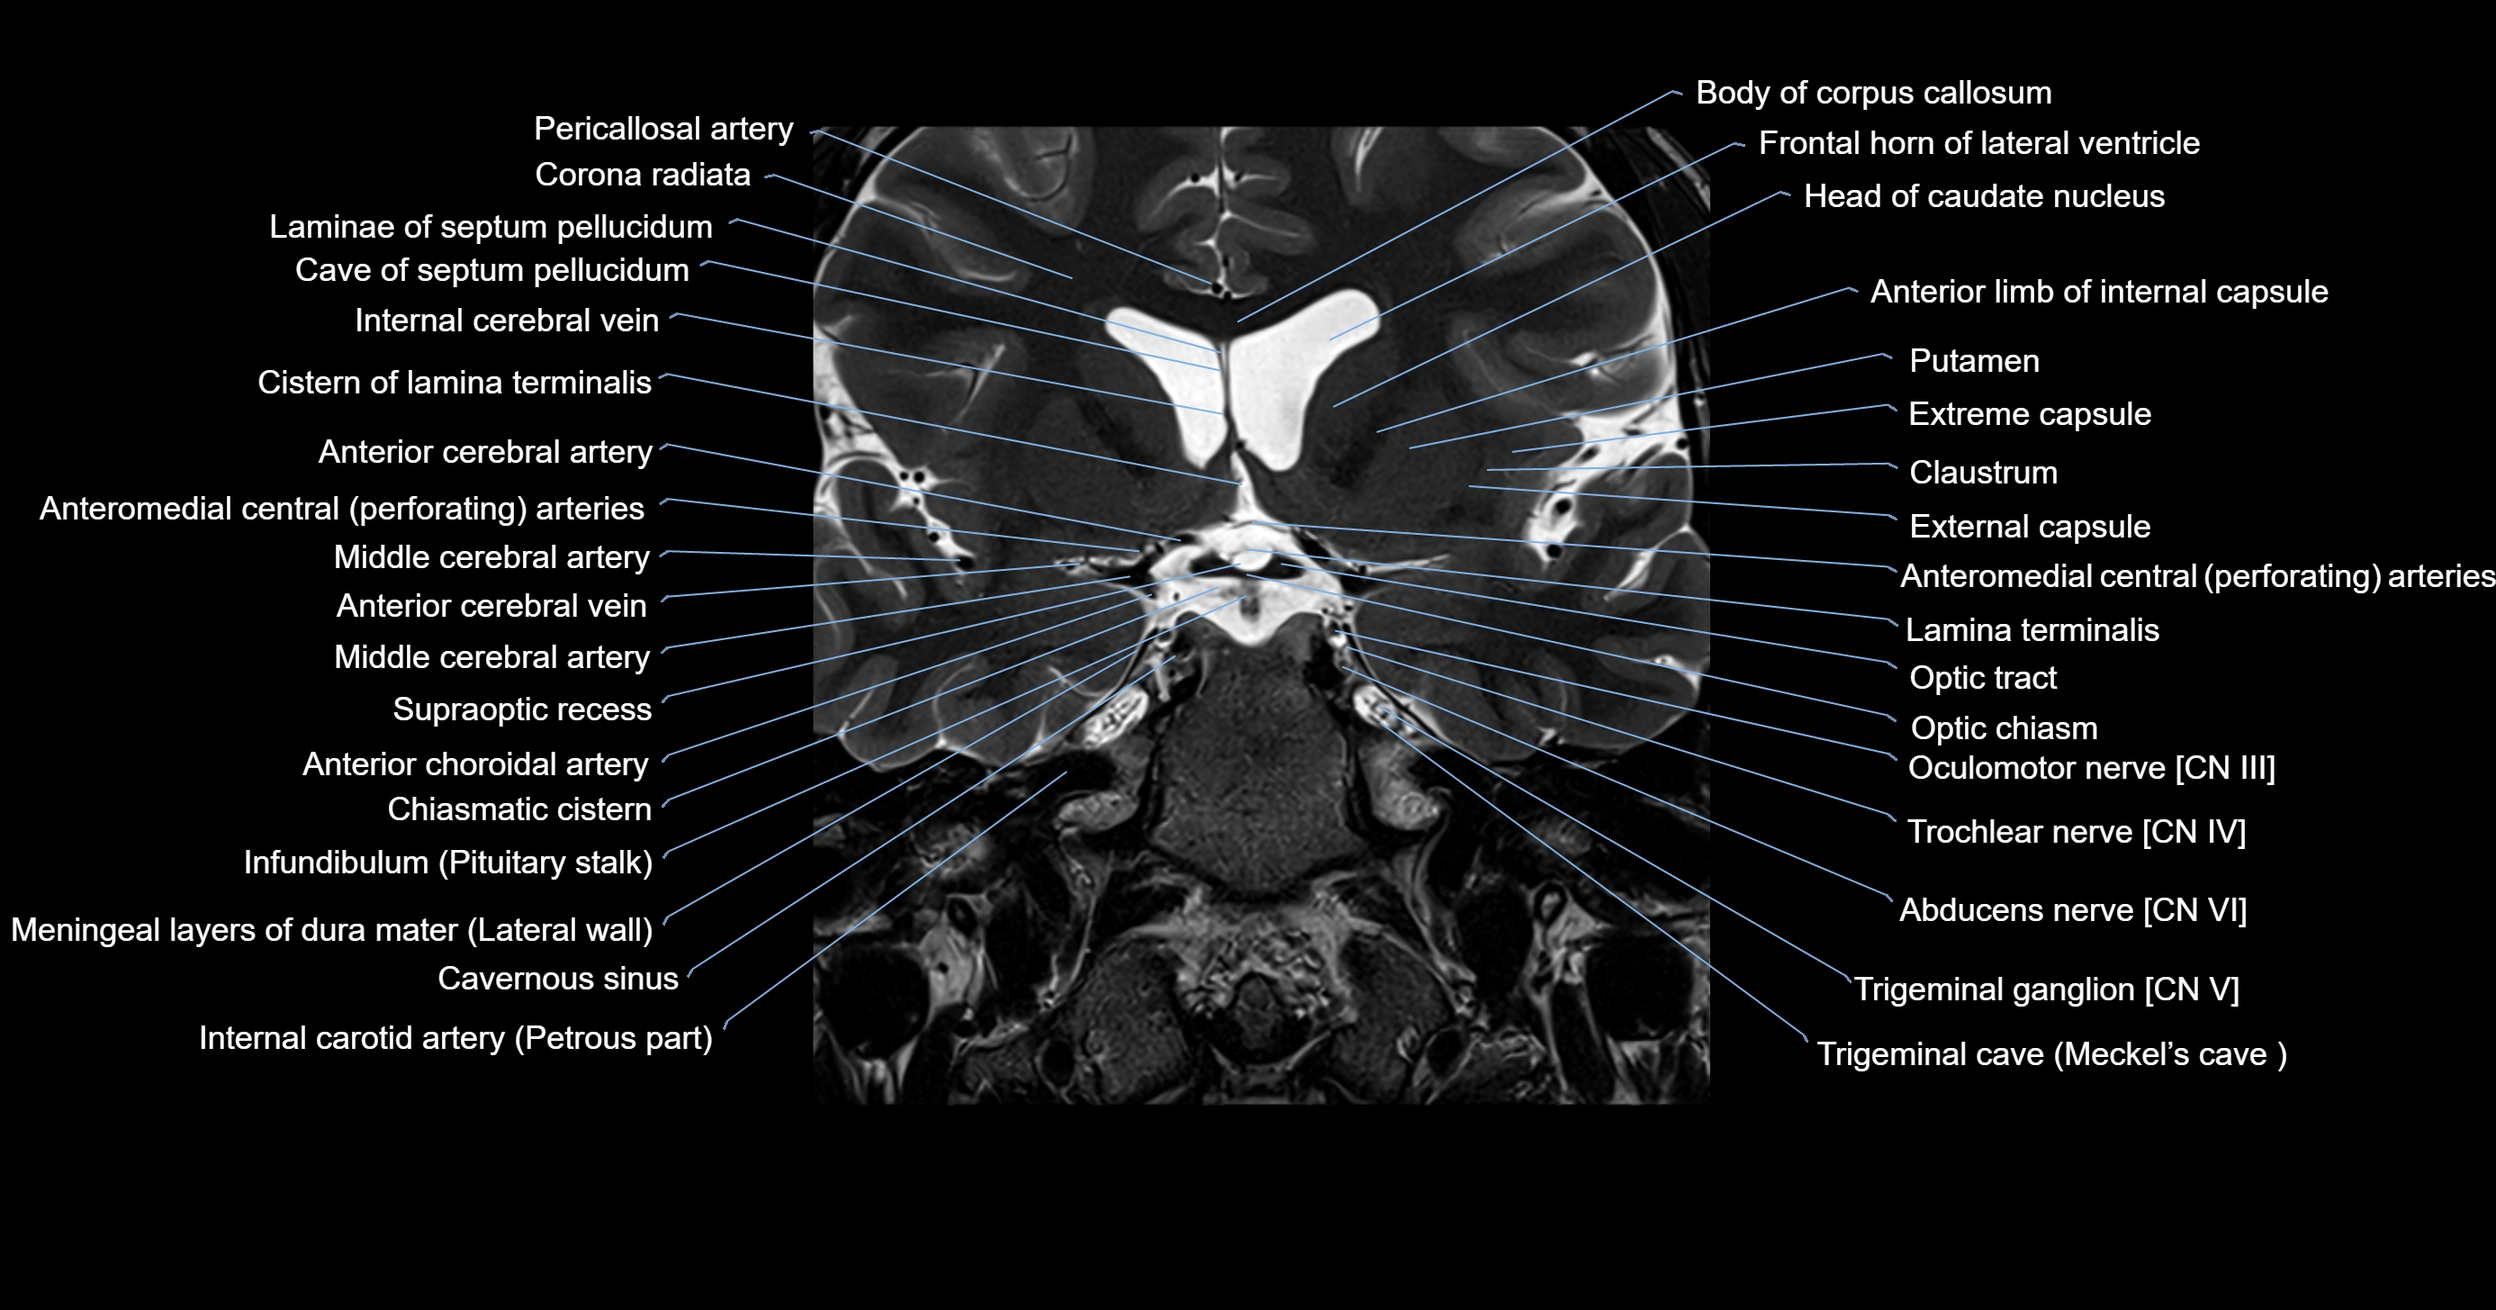

MRI images